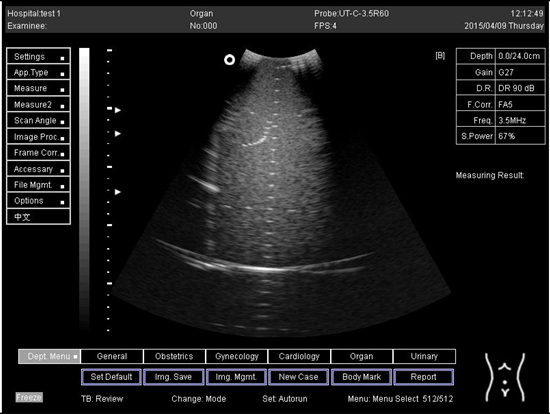

Table A5. The image taken for focal zone determination in different depth for curve probe.

Depth (cm)Diagram

14.0Biomimetics 07 00130 i031

16.0Biomimetics 07 00130 i032

18.0Biomimetics 07 00130 i033

24.0Biomimetics 07 00130 i034